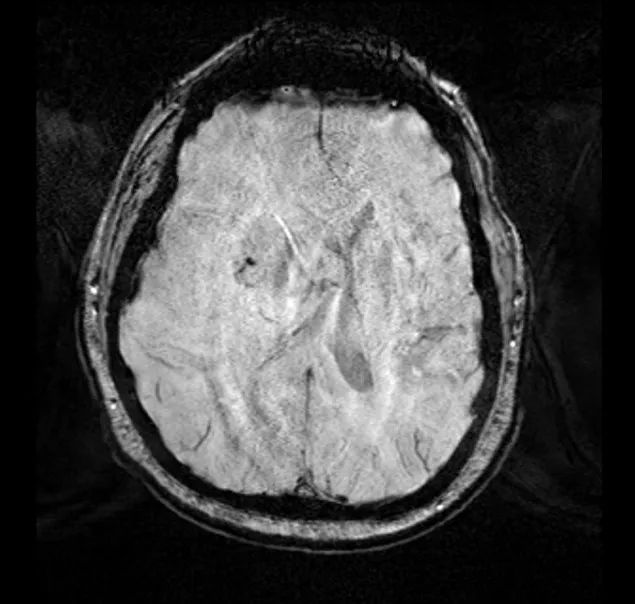

术后患者安返神经ICU。 术后使用地塞米松并于1周内迅速减量撤药。 使用左乙拉西坦500mg bid预防性抗癫痫。 术后第1天复查MRI见肿瘤近全切。

最终病理与活检结果一致,均为转移性低分化癌。 术后第5天患者出院回家,无神经功能障碍,残余肿瘤计划行立体定向放疗,同时建议患者肿瘤科随诊,以处理系统性病变。

手术切除单发、大型、症状性且手术可及的脑转移瘤能够提高患者的总体生存率。[1,2] NICO公司设计生产的BrainPath是一套经脑沟入路切除肿瘤和清除血肿的设备,具有皮层下结构无损伤的特点。[3] 激进切除位置深在的脑转移瘤往往造成严重并发症。因此传统上该类肿瘤采用姑息疗法:立体定向穿刺活检、放疗和药物治疗。[4] 本病例所采用的技术非常适用于侵犯基底节或者位于脑室旁的深部皮层下原发或继发性肿瘤。[4,5] 基于通道理念设计的牵开器(channel-base retractor)作用在于撑开而不是离断白质传导束,并为到达和切除肿瘤创造一个具有保护作用的手术通道,因此能够最大程度避免组织误伤,降低缺血事件和传导束损伤的风险。[4,6,7]